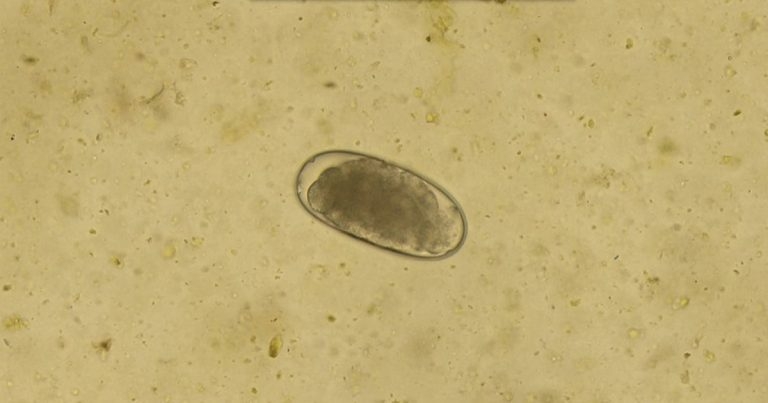

Zoetis has expanded its multi-purpose diagnostics platform Vetscan Imagyst to include artificial intelligence (AI) equine faecal egg count (FEC) analysis.

“This technology is proven to be as accurate at identifying Strongyle species and Parascaris species as a board-certified parasitologist, delivering fast, reliable and shareable results within 10 minutes.”